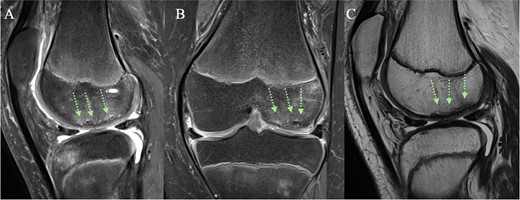

(A + C) Sagittal and (B) coronal MRI views 4 months post-operatively. The arrows indicate healing of the chondral fracture, although some minor subchondral abnormalities are present.